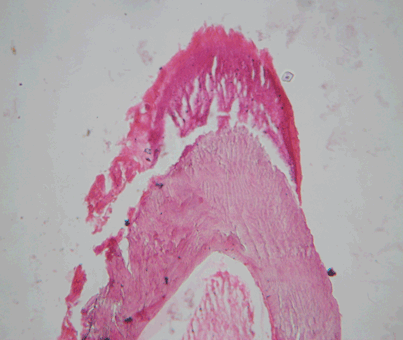

After decalcification and routine histopathological processing, the microscopy showed varying amounts of enamel matrix, dentin and pulp-like tissue (Figure 3) and (Figure 4).

Cursor on image to zoom/Click text to open image

Figure 3: Decalcified section showing enamel matrix, dentin and pulp like tissue (H&E stain, x40).

Figure 4: Decalcified section showing enamel matrix, dentinal tubules (H&E stain, x40).